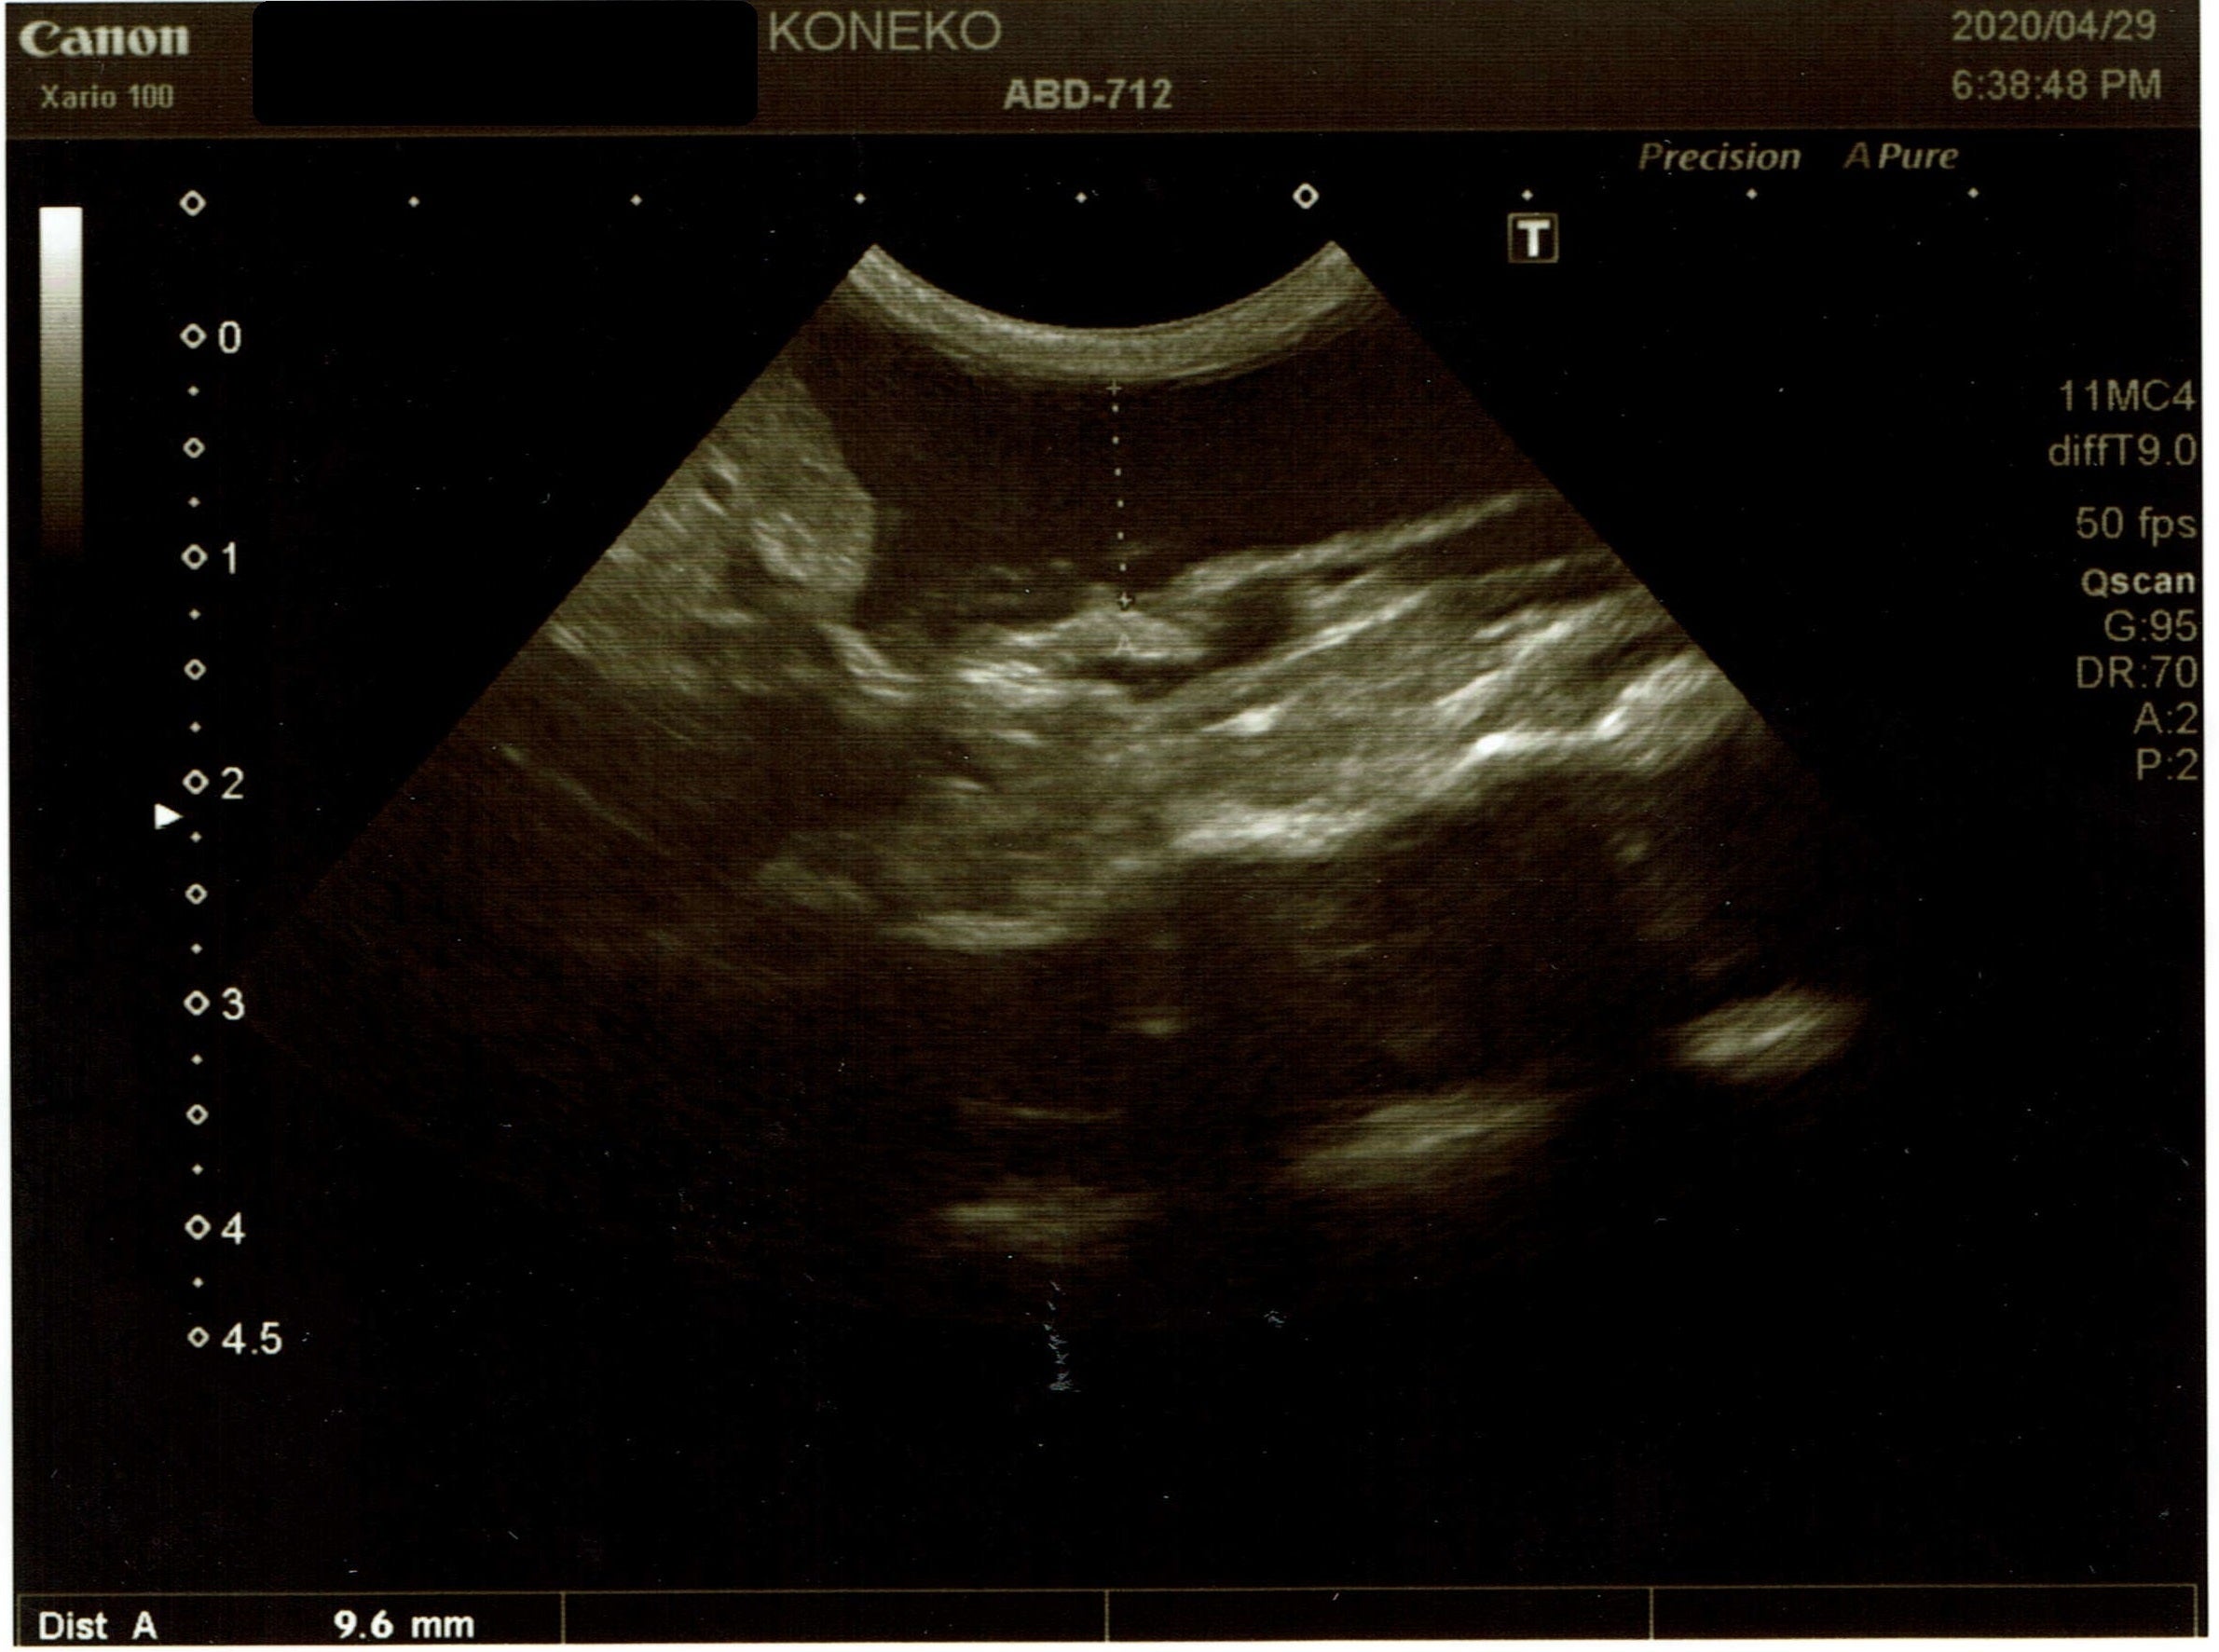

4月29日

ルゥナは、自宅に来てからずっと一日の半分くらいしかごはんを食べておらず、

なのに、お腹がパンパンだな(腹水かな?)と思い、ネットで検索したところ、

FIPがヒットし、初めて『FIP』という病気があることを知りました。

ただのおデブちゃんか、FIPか診てもらおうとA動物病院へ。

↑

1〜2㎝の腹水貯留あり腹部エコーと腹水穿刺の結果、恐らくウェットタイプのFIPで間違いないだろうと。

腹水の検体を検査に出して、猫コロナウイルス陽性の結果であれば、FIP確定だと説明されました。